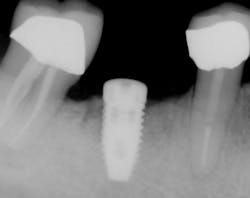

With ridge split bone augmentation, Dr. Sawyer surgically placed the implant at tooth 30 in August 2007. The crown for the implant was placed the following February. By April 2009 the implant had become infected and suppurant, and the bone support around the implant was ailing with four threads affected.

Implant for tooth #30 at surgical placement